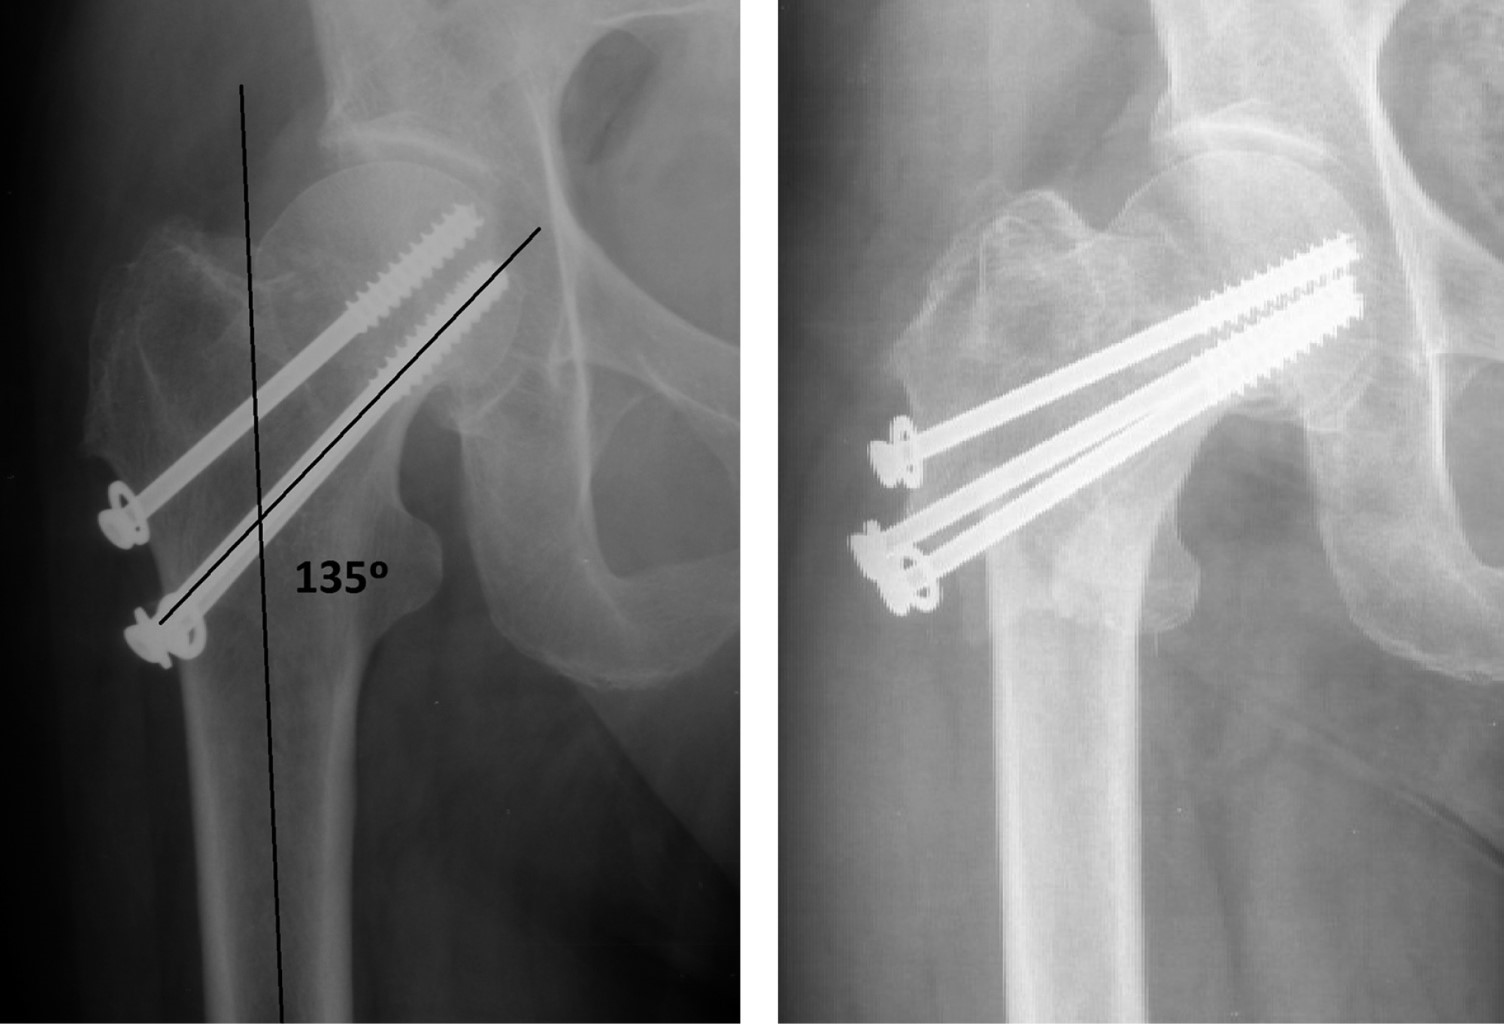

Periosteosynthesis subtrochanteric fractures after fixation of femoral neck fractures with cannulated screws

Introduction: the objective of this study was to analyze the incidence and predisposing factors in subtrochanteric fractures on hips previously treated with cannulated screws after suffering a subcapital fracture, based on eight cases registered in the last 20 years. Material and methods: this is a retrospective observational study on a series of patients with a diagnosis of subtrochanteric hip fracture, who have been treated in recent months for a subcapital fracture of the same hip by osteosynthesis with cannulated screws. The study period was 20 years (2000-2020). Results: of the eight cases, five were women and three were men, with a mean age of 75.12 years (range 59-87 years). In all cases, the subtrochanteric fracture occurred within a year after the first fracture, the time elapsed between the two fractures was four months on average (range 1-9 months). Regarding the disposition of the cannulated screws, most of the 7/8 cases were in the shape of an upper vertex triangle, and only one case was in the shape of an inverted triangle or lower vertex. The entry point into the femoral external cortex was at the level of the lesser trochanter in six cases, and in two cases this entry was distal to the lesser trochanter. Conclusion: in our experience, in the etiology of subtrochanteric fractures, the introduction of screws distal to the lesser trochanter, and the distribution of the screws in a triangular shape are the two main objective predisposing factors.

Figure 5

Figure 6